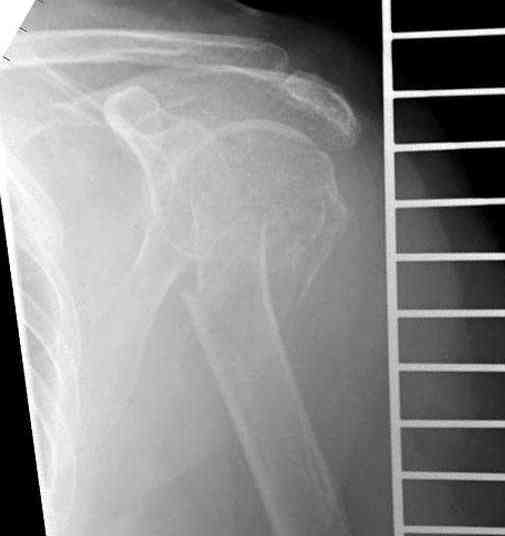

[Ortho] Оскольчатый перелом шейки, головки плечевой кости

Имя     : 1 Proximal humerus CRM.jpg

Имя     : 1 Proximal humerus injury.jpg